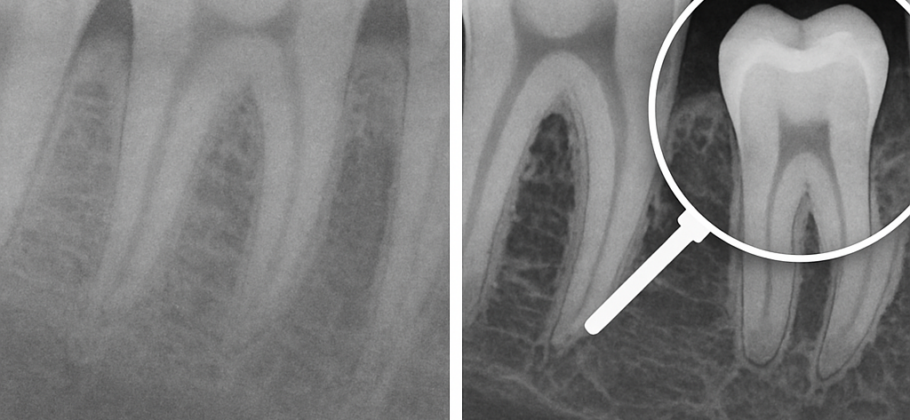

Uno de los pilares de este enfoque es el diagnóstico por imagen. La radiografía panorámica digital, por ejemplo, sigue siendo una herramienta muy utilizada para la primera valoración porque permite observar de manera global dientes, hueso y estructuras relevantes. En su versión digital, facilita la visualización, el almacenamiento y la comunicación clínica. Para pacientes que quieren informarse antes de su cita, La Clínica Dental publicó una guía práctica sobre el tema: https://laclinicadental.org/rayos-x-panoramicos-digitales-vs-convencionales-beneficios-y-como-funcionan/.